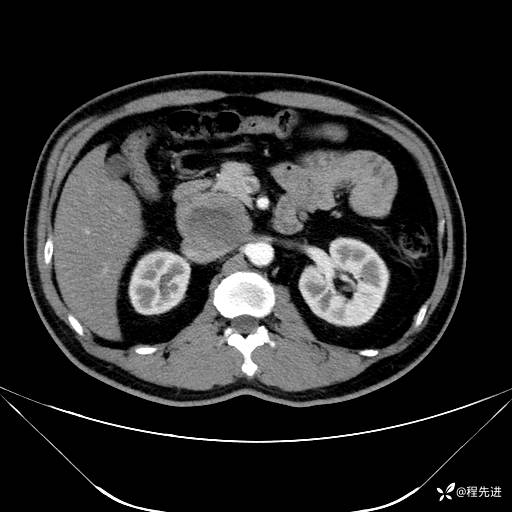

【腹盆】特别精彩病例|发现腹膜后肿物1月余

患者年龄:42岁

主诉:发现腹膜后肿物1月余

现病史:患者1月余前查体,行超声检查提示:后腹膜囊实性肿块;慢性胆囊炎伴胆囊内结石;无腹痛腹胀,不伴腹泻发热等;偶感腰背部酸痛。

CT平扫+增强: